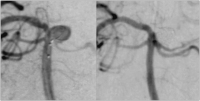

Abbildung 3: Aneurysma der Arteria cerebelli superior links. Links: Einbringung des ersten Coils. Rechts: Nach Beendigung des Eingriffs.